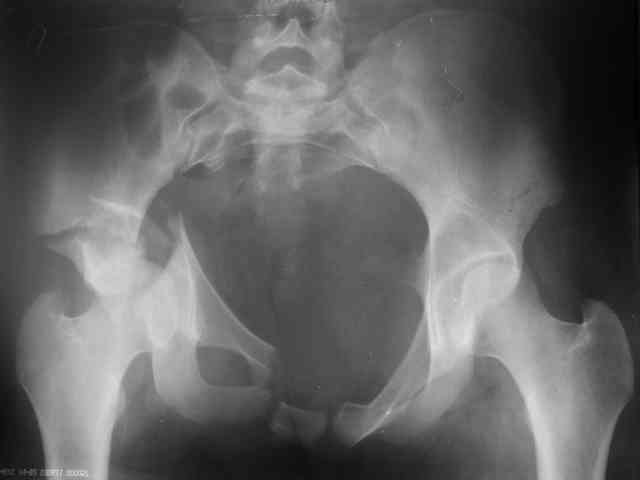

Трудности возникли сразу после рассечения большой ягодичной мыцы - короткие наружные ротаторы едва ли определялись - головка и шейка (как видно на

снимке) ушли в таз, пришлось воспользоваться дистрактором( ручные попытки выдернуть голову из под проксимального фрагмента - безуспешны) Шарнирный дистрактор - великое изобретение, без него репозиция была просто невозможна.